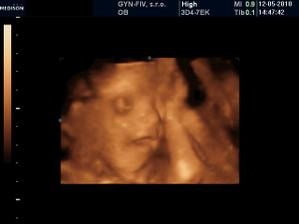

Náš chrústik - "Becky" 🙂